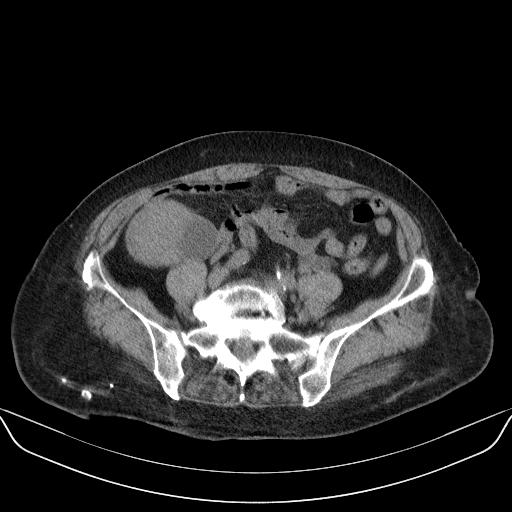

以下是引用yuhongjun在2010-3-12 6:32:00的发言:[br]回肠末端间质瘤,不除外阑尾粘液囊腺瘤,臀部注射性肉芽肿钙化. [br] [br]